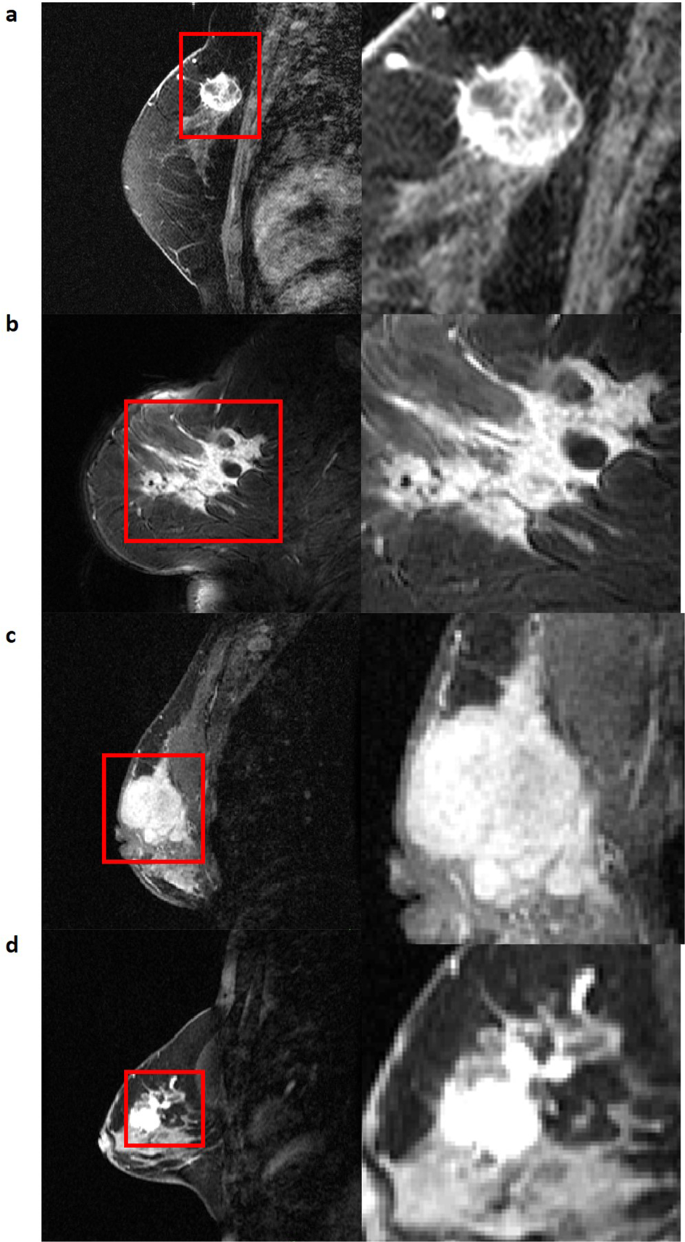

The FTV annotations were quantitatively compared with the corresponding STV annotations using the Dice score in order to quantify the difference between the two annotations. Additionally, a qualitative analysis was performed for the best and worst performing cases (illustrated in Fig. 3).

Three representative single slice tumor segmentations. (a) First-post contrast image of entire breast. (b) Primary tumor region of interest. (c) Functional tumor volume (FTV) segmentation (d) Structural tumor volume (STV) segmentations which have been expert annotated. Rows showcase different representative images for each case.